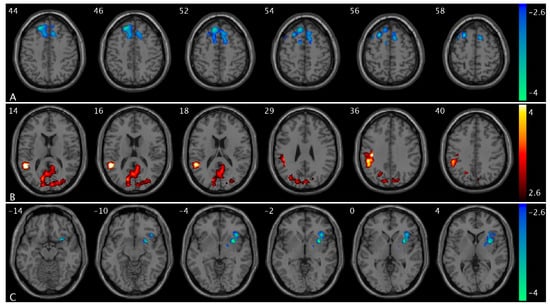

We observed significant CBF changes from low- to high-urge states in healthy controls and OAB participants separately. Specifically, when bladder filling increases from a low- to high-urge state, we found CBF increases in the superior frontal, superior medial frontal, anterior cingulate, and supplementary motor regions in healthy controls (Figure 2A) but no CBF changes in these regions in OAB participants and CBF decreases in the supramarginal, middle, and superior temporal regions in healthy controls (Figure 2B) but no CBF changes in these regions in OAB participants; we also found no significant changes in healthy controls but CBF increases in the precuneus, cuneus, and superior occipital regions in OAB participants (Figure 2C). A summary of these clusters’ statistics is reported in Table S1.

We observed significant changes in PCC FC from low- to high-urge states in healthy controls and OAB participants separately. Specifically, when bladder filling increases from low- to high-urge states, we found PCC FC increases in the superior frontal, superior medial frontal, insula, putamen, caudate, middle temporal, and middle occipital regions in healthy controls (Figure 3A and Figure S1C) but no PCC FC changes in these regions in OAB participants; and PCC FC decreases in the postcentral and superior parietal regions (i.e., sensorimotor network area) in healthy controls (Figure 3B) but there are no PCC FC changes in these regions in OAB participants. A summary of the clusters’ statistics is reported in Table S1.

Figure 2. Statistical maps overlaid on T1-weighted images showing altered CBF from low- to high-urge state in healthy controls and OAB participants. (A) CBF increases in the superior frontal, superior medial frontal, anterior cingulate, and supplementary motor regions in healthy controls; (B) CBF decreases in the supramarginal, middle, and superior temporal regions in healthy controls; (C) CBF increases in the precuneus, cuneus, and superior occipital regions in OAB participants from low- to high-urge state. The numbers in the top left corner of the MRI images indicate the z-coordinate (in mm) in the MNI space. The color bars represent t-values.

Figure 3. Statistical maps overlaid on T1-weighted images showing altered PCC FC from low- to high-urge state in healthy controls and OAB participants. (A) PCC FC increases in insula, putamen, and caudate in healthy controls (within the same slice range as in Figure 1C); (B) PCC FC decreases in the postcentral and superior parietal regions in healthy controls. Additional increased PCC FC regions are shown in Figure S1C. The numbers in the top left corner of the MRI images indicate the z-coordinate (in mm) in the MNI space. The color bars represent t-values.